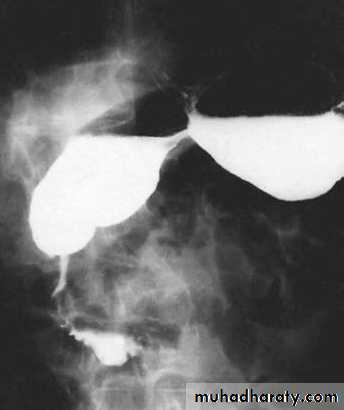

Volvulus of the stomach

Rotation around its fixed points (cardia & pylorus):• Horizontal (Oraganoaxial).

• Vertical (Mesenteroaxial).

• Usually associated with diaphragmatic hernia, eventration of diaphragm.

• The transverse colon moves upwards taking the

stomach with it & both may enter the chest